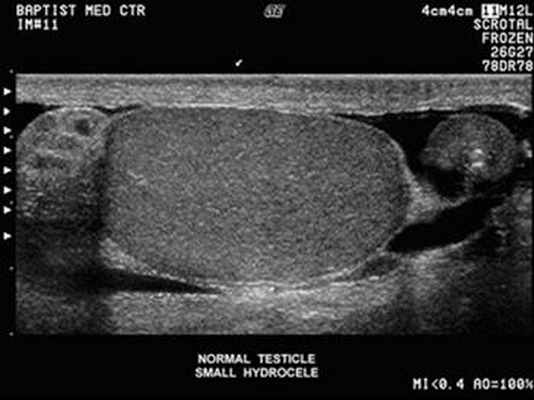

в выявлении патологических изменений надпочечников и предстательной железы –

гиперплазии, воспалительных изменений, кист и опухолей. УЗИ мошонки позволяет детально

изучить состояние яичка, его придатков и семенного канатика.

УЗИ мошонки, воспаление яичка.